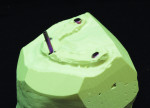

Guide pins are then screwed into implant model analogs, allowing the denture to line up to the milling machine when drilling screw access holes (Figure 22, Figure 23 and Figure 24).